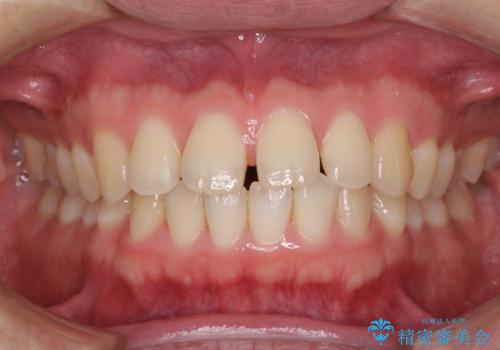

すきっ歯の改善 インビザライン矯正治療

- 上の前歯の隙間を気にして来院された患者様です。

インビザラインにより、上下の歯列を側方に拡大しつつ、前歯の隙間を閉じていくこととしました。

1日22時間の装着時間をしっかりと守ってくださったので、隙間がきれいに閉じ、口元の突出感も改善することができました。